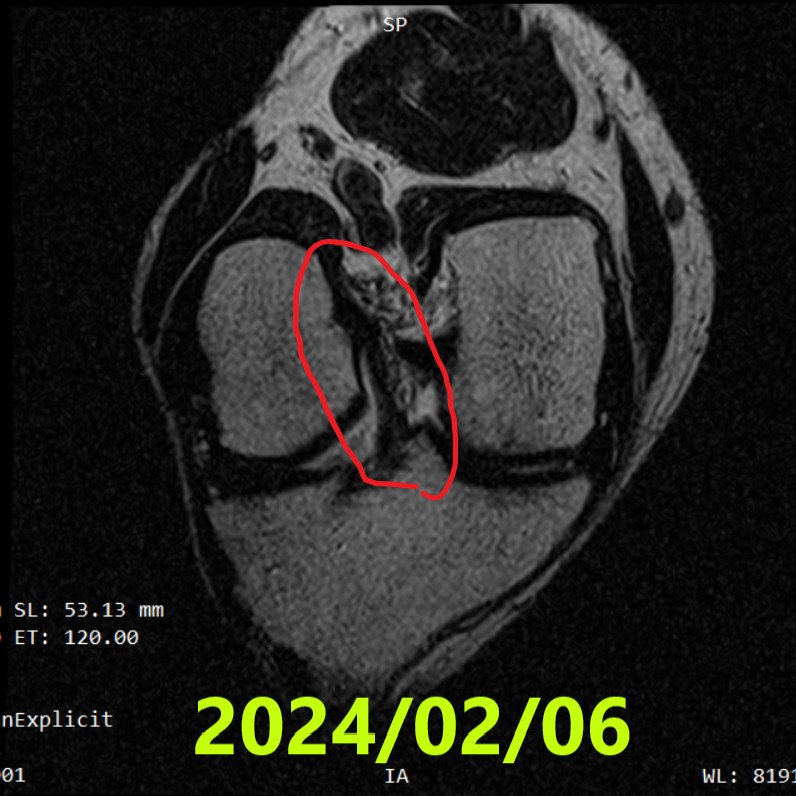

Terza RM(~11 mesi)

- Data: 6 febbraio 2024

- Reperti: nessuna variazione maggiore; la continuità del LCA è chiaramente mantenuta

- RM #3(06/02/2024): continuità mantenuta; attività quotidiane senza problemi